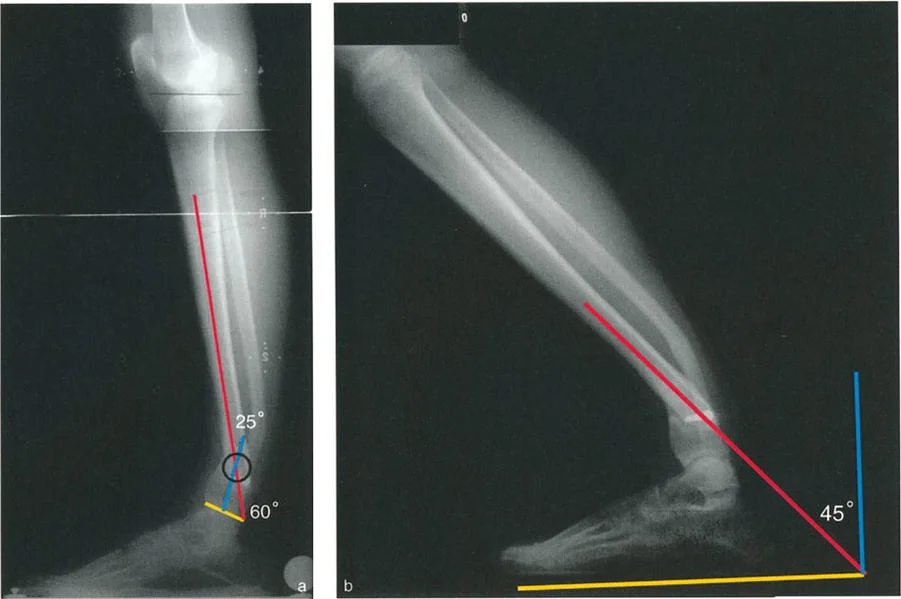

* الأشعة السينية الجانبية والامامية الخلفية للكاحل: تُظهر هذه الصور تفاصيل مفصل الكاحل نفسه، بما في ذلك زاوية القصبة الأمامية البعيدة (ADTA) وزاوية القصبة الوحشية البعيدة (LDTA)، وهي زوايا حاسمة لتحديد التشوه في المستويين الأمامي والسهمي.

* رسم المحاور الميكانيكية والتشريحية: لتحديد نقطة مركز دوران التشوه (CORA)، وهي النقطة التي يجب أن تتم عندها الجراحة لتصحيح التشوه بأقل قدر من المضاعفات.

* فهم آليات التعويض: تحليل كيف تحاول القدم والكاحل تعويض التشوه في الساق، وما هي حدود هذا التعويض.